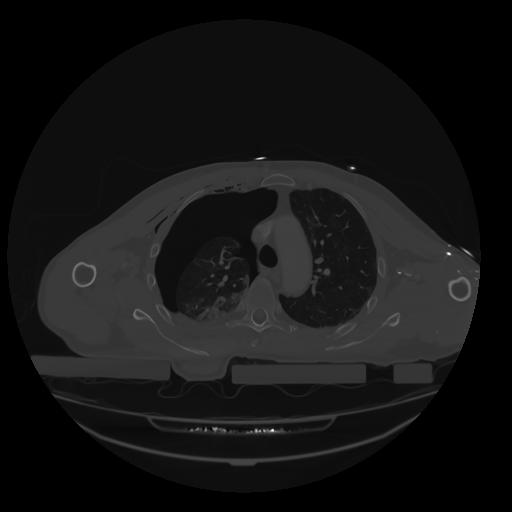

28 CUERPO,CE,Vol,2.0,CUERPO,,